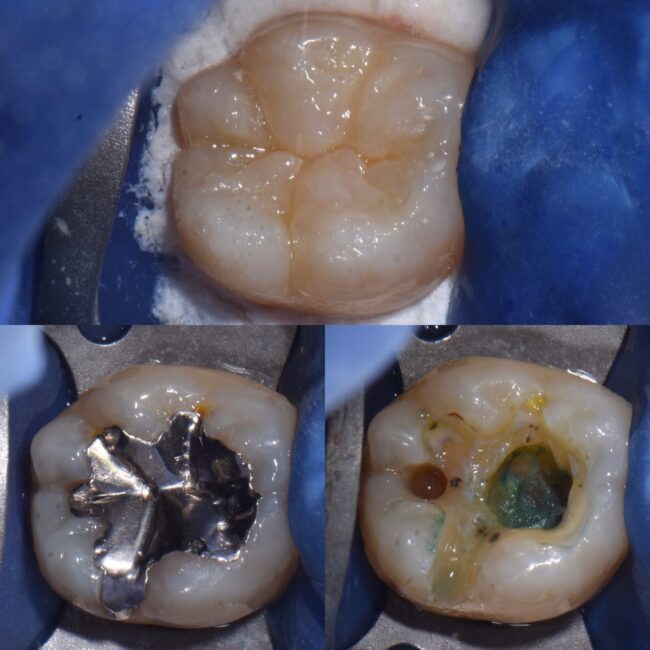

専門医が行う根管治療②ラバーダム防湿の有用性 〜宇部市歯医者(歯の神...